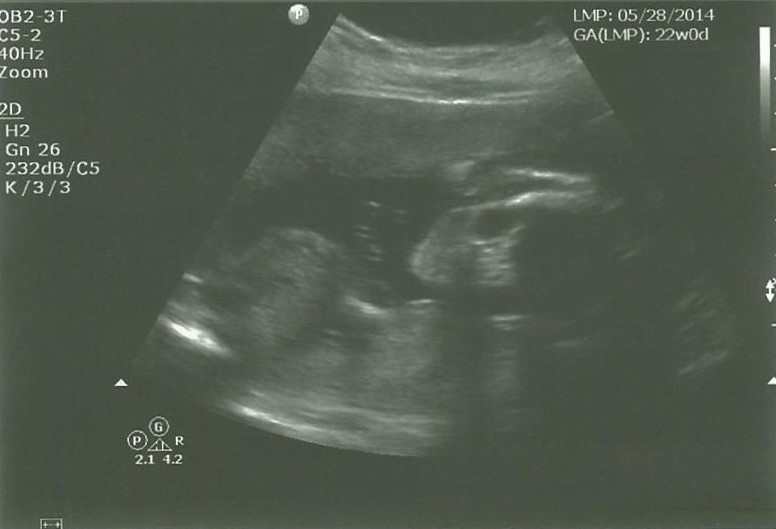

So, I'm Jess. I'm 26 years old. My husband and I are expecting our first child. We are 20 weeks along and find out the gender today. I would be lying if I said I'm not nervous. Of course I'm nervous. This is all brand new to me. I've had a hell of a time so far. Since week 9 I have had hellish morning sickness.